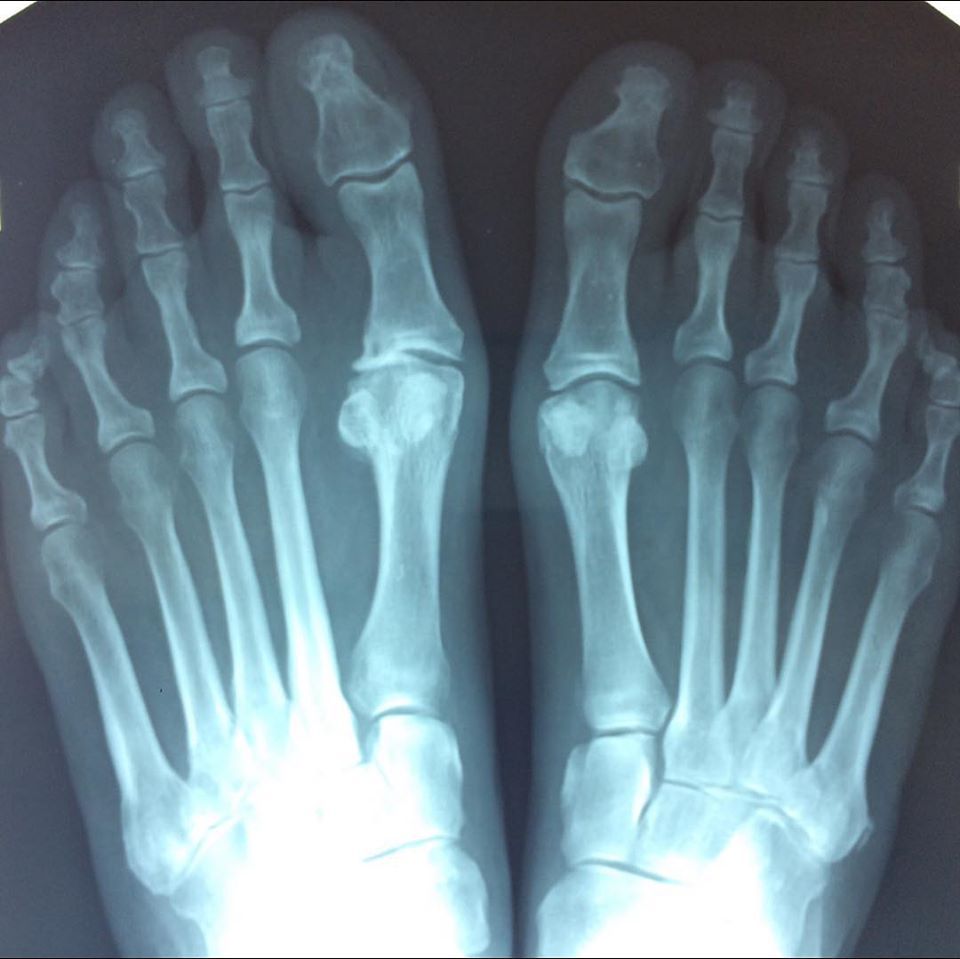

Il dott. Testi si occupa con competenza di una vasta gamma di disturbi e patologie podologiche, tra cui:

- Micosi e altre infezioni fungine

- Unghie incarnite

- Calli e duroni

- Lesioni cutanee

- Ulcere del piede diabetico

- Verruche plantari

- Condizioni dolorose degli arti inferiori, come fascite plantare, tendiniti e disturbi muscolari